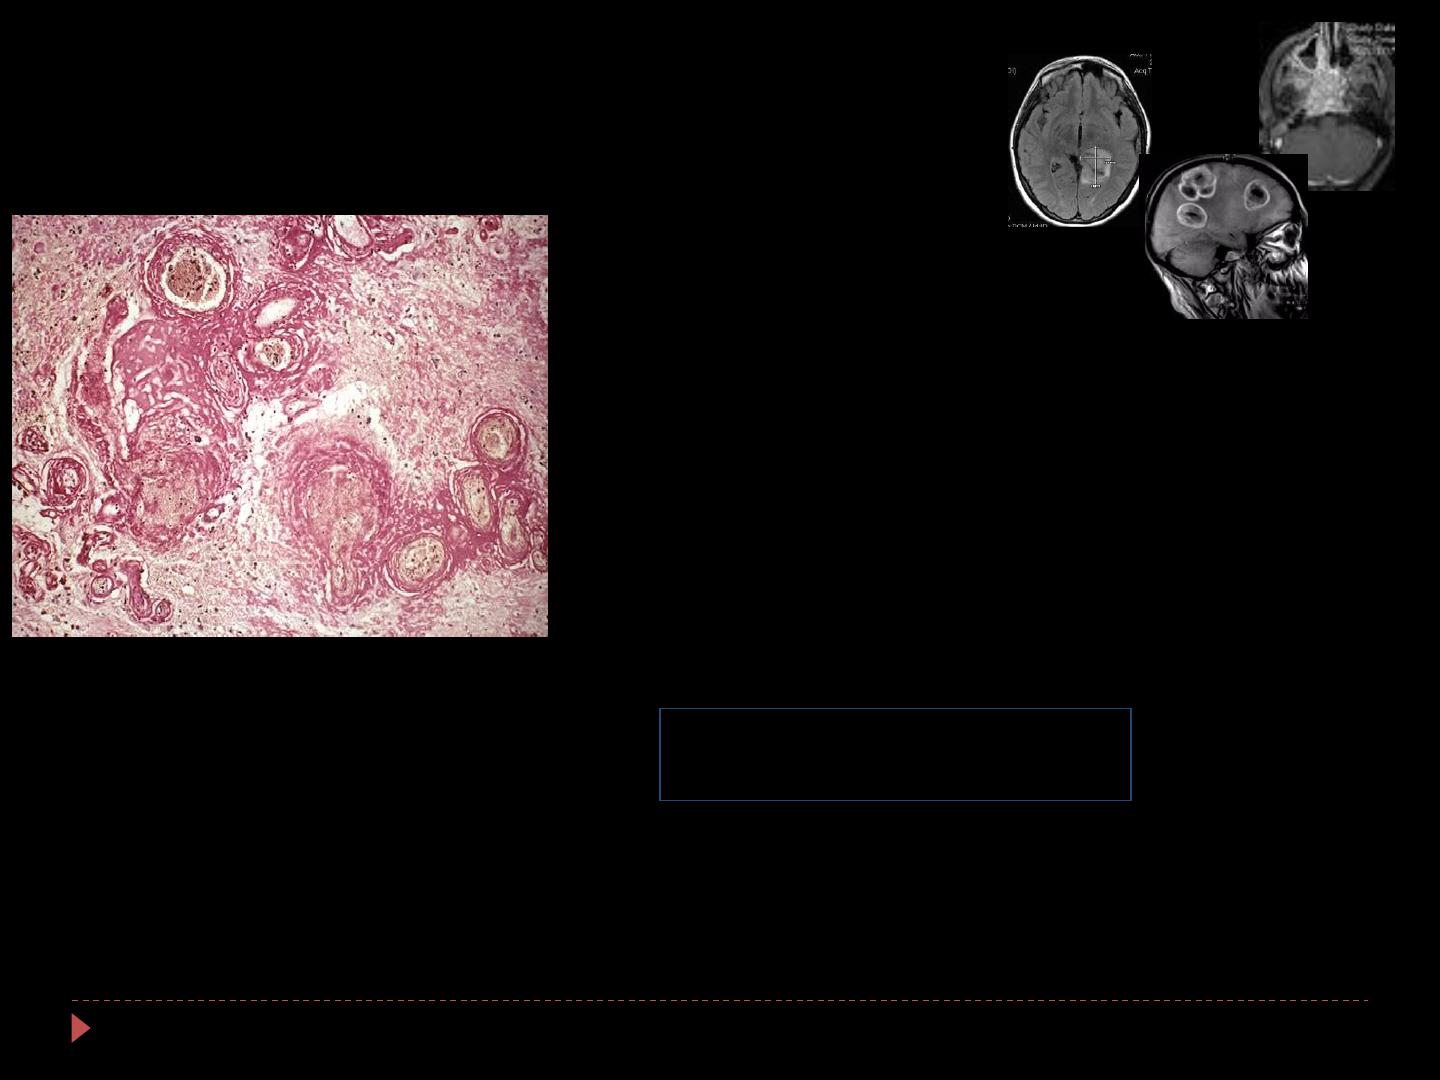

Radionécrose focale

1

Bevacizumab ?

Chirurgie

Corticoïdes

Anticoagulants

Oxygénothérapie hyperbare

Autres…